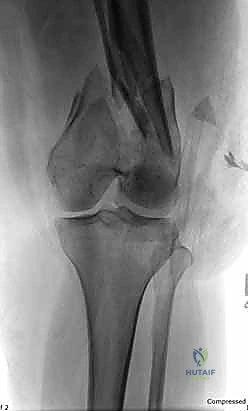

- الأشعة السينية (X-Rays): أخذ صور من زوايا متعددة (أمامي خلفي، وجانبي) لتحديد موقع الكسر ونوعه.

- الأشعة المقطعية (CT Scan): وهي ضرورية جداً في كسور عظم الفخذ البعيدة، خاصة إذا كان الكسر يمتد إلى داخل مفصل الركبة (Intra-articular fractures). تساعد الأشعة المقطعية الدكتور هطيف على بناء نموذج ثلاثي الأبعاد للكسر، مما يسهل التخطيط الجراحي وتحديد أماكن وضع المسامير بدقة.

المرحلة الثالثة: إرجاع العظم (Reduction)

هذه هي الخطوة الأكثر أهمية. يقوم الدكتور هطيف بإعادة القطع العظمية المكسورة إلى مكانها التشريحي الأصلي. إذا كان الكسر ممتداً داخل المفصل، يتم تثبيت السطح المفصلي أولاً باستخدام مسامير دقيقة لضمان سطح أملس يمنع الاحتكاك والخشونة مستقبلاً.